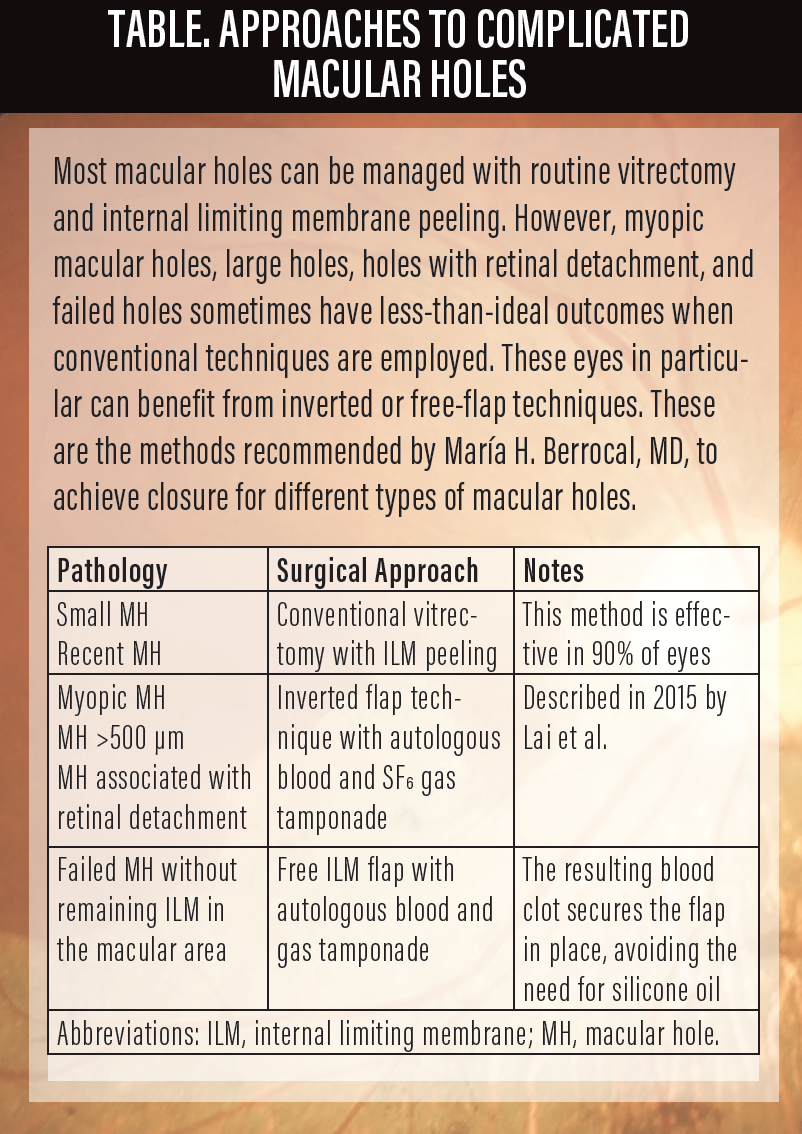

Figure. OCT of localized retinal detachment associated with macular hole in a 60-year-old woman with -10 D. VA was counting fingers (A). OCT 6 months after vitrectomy with inverted flap and autologous blood technique. Macular hole closed and VA improved to 20/200 (B).

Excellent anatomic closure rates are seen with this technique as well as visual improvements, although the visual outcomes depend on the size of the hole, atrophy (in myopic patients), duration of retinal detachment (in holes associated with myopic detachments), and RPE status (Figure).